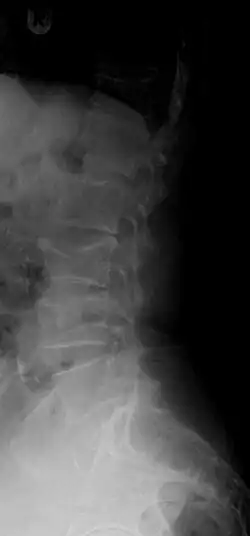

Compression fracture of T12